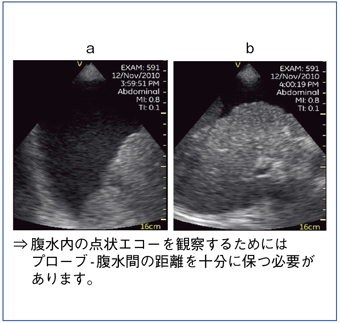

図7は,原発性肝細胞がん破裂例である。Vscanでは,浅部の描出をやや苦手としているため,本症例においても図7 aでは腹水内の血液が点状エコーとして描出されていない。しかし,視野の中心に対象が来るようにプローブを走査し,プローブと腹水の間の距離を十分に保つことで,より細かい観察が可能となる(図7 b)。

図7 症例2:原発性肝細胞がん破裂